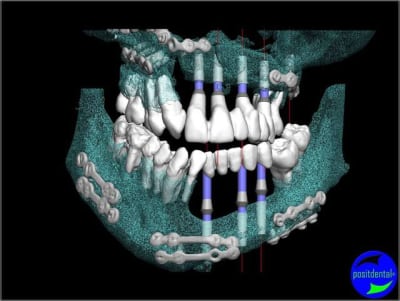

et la projet 10 implants maxillaire sup

en une fois avec les 2 sinus ou séparé?

5+5 ou 10+10

10 en haut

donc ce sera minimum 8 en fonction du scan